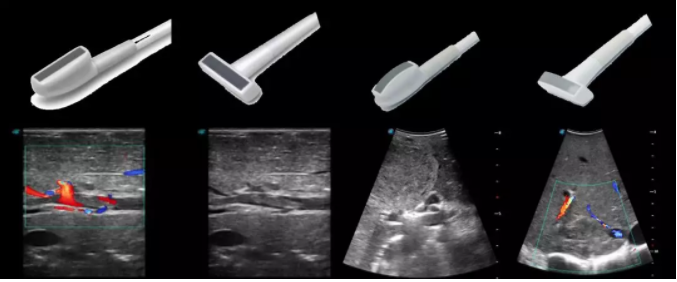

線陣/凸陣不同選擇,多種外形設(shè)計可以滿足適用于不同的臨床科室,滿足不同醫(yī)生的使用需求;

輕便小巧,方便持握;

防水、易消毒;

應(yīng)用科室:手術(shù)室、肝膽外科、消化外科、腫瘤科、心胸外科、泌尿外科、婦產(chǎn)科等